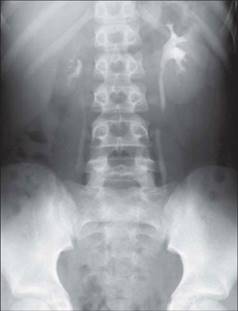

Рентгенограма хворих з СМР